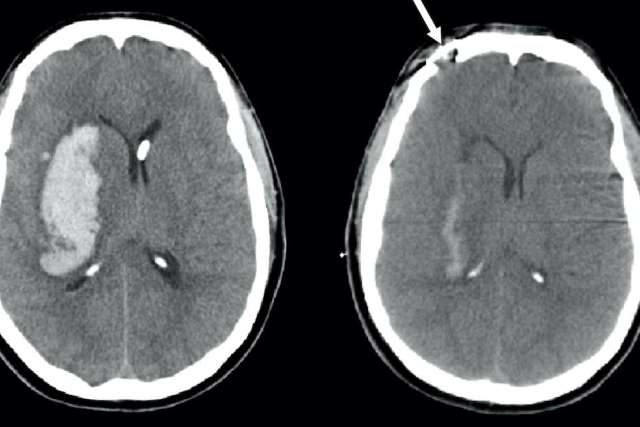

A stroke occurs when the blood supply to a certain part of the brain is interrupted, such as by a blood clot. Brain cells in that area become damaged and can no longer function. Depending on which part of the brain has been damaged, the skills lost after the stroke may include motor skills, speech or sensory perception.